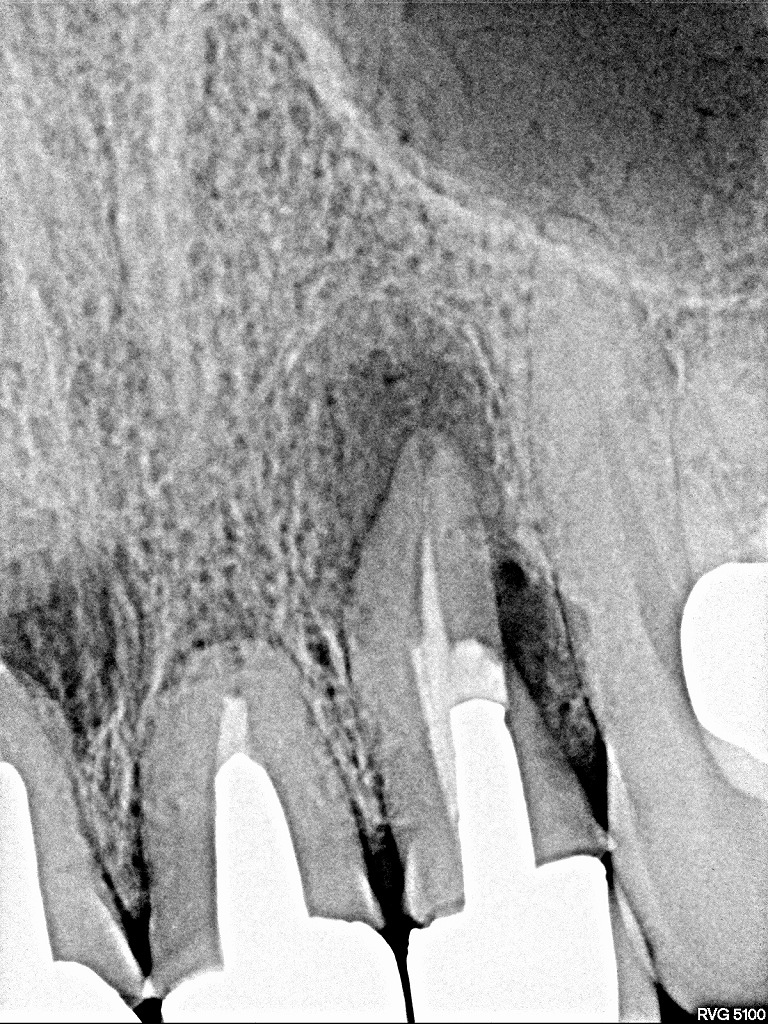

レントゲンにてもパーフォレーションを認めるとともに

根尖病巣も大きく存在しています

こちらの歯は外科処置もしてあり病巣も大きく存在しています